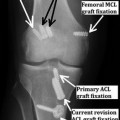

Fixation in Revision ACL Reconstruction